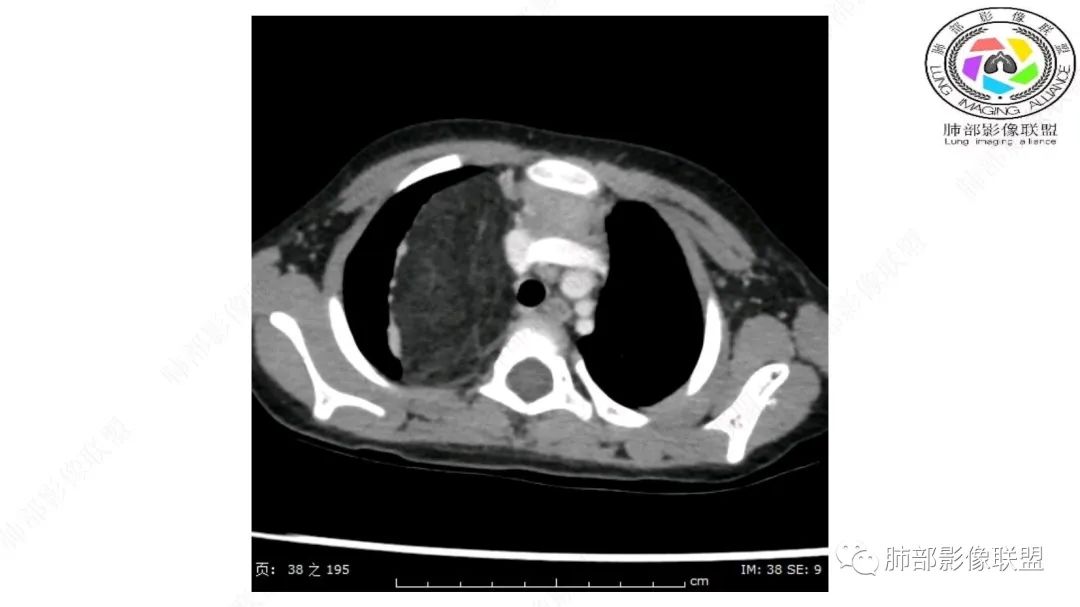

右上纵隔混杂密度肿块,边缘光整,与纵隔分界清,其内多发脂肪密度,增强无明显强化,其内血管穿行,考虑纵隔脂肪母细胞瘤,鉴别畸胎瘤,脂肪肉瘤。

患儿3岁 咳嗽检查发现纵隔占位。右肺上叶受压表现,占位以脂肪组织密度为主,似见分隔,首先考虑为脂肪母细胞瘤,鉴别脂肪瘤,畸胎瘤。

病灶属于交界区,主体位于肺内,占位效应明显,前方突入胸壁,胸腺受压变形,胸膜显示欠清楚;病灶包绕上叶肺动脉;似乎有体动脉供血。符合肺内的点:包绕上叶肺动脉分支;符合纵隔的点:前方似乎突入胸壁,与胸腺关系比较密切,但是与上腔静脉的关系提示病灶不支持纵隔来源,前纵隔的常规会将上腔静脉受压后移、外移,这是不符合的。

手术记录:见右肺上叶肿物,肿物与右肺上叶关系密切。与纵隔无粘连,逐步分离肿物,见肿物大小约6cm*5cm,边界清楚,于右肺上叶粘连,边界清楚,肿物包绕右肺上叶血管及支气管。超声刀逐步游离肿物,完整切除肿物,右肺上叶肺组织无破溃,表面无出血。

1.右上肺-纵隔交界区巨块影,主体位于右肺一侧,紧贴胸腺、头臂干、右锁骨下动脉、上腔静脉、奇静脉等,不能分离,但病灶整体边界清楚。注意上述相邻腔静脉等结构未见受压变形,纵隔亦未见明显向左推移,至少提示两点:

2.肺动脉穿行也许是肺内来源最重要支持点!